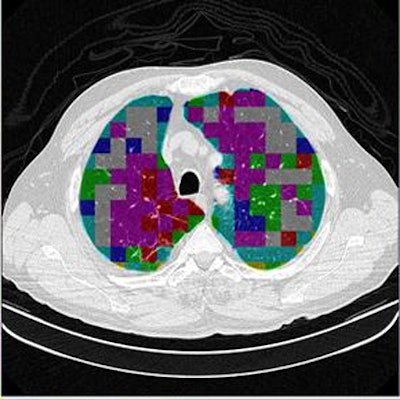

Two of the nine classes, background and outside tissue, indicate regions outside the lungs. The remaining seven classes refer to patterns found in the lungs: normal parenchyma, ground-glass opacities, reticular and linear opacities, nodular opacities, honeycombing, emphysematous change, and consolidation.

In the last step, postprocessing, each pattern type is assigned a color label and the DICOM file is rebuilt. The communication/archiving agent finishes off the process by including the image slices with the labeled ROIs as a new image series in the exam and sending it back to the PACS server. The color coding allows radiologists to easily see which lung regions might be affected by a particular type of diffuse lung disease.

![]() |

| The classification algorithm training and test was performed using a 10-fold cross-validation methodology, which classified regions of interest in the lung parenchyma into nine patterns commonly seen on thoracic high-resolution CT images. The background and outside tissue classes indicate regions outside the lungs, while the remaining seven classes refer to patterns found in the lungs: normal parenchyma, ground-glass opacities, reticular and linear opacities, nodular opacities, honeycombing, emphysematous change, and consolidation. The classification step delivered an initial average accuracy of 61.6% (above). Eliminating the two most frequently confused categories, ground-glass opacities and consolidation, improved the average classification accuracy to 78%. |

| The completed CAD-analyzed cases are stored as a new series in the PACS server, where they can be examined side by side. In the color-coding system, normal parenchyma is white; ground-glass regions are blue; reticular-linear, green; micronodules, red; honeycombing, yellow; emphysematous changes, magenta; and consolidation, cyan. |